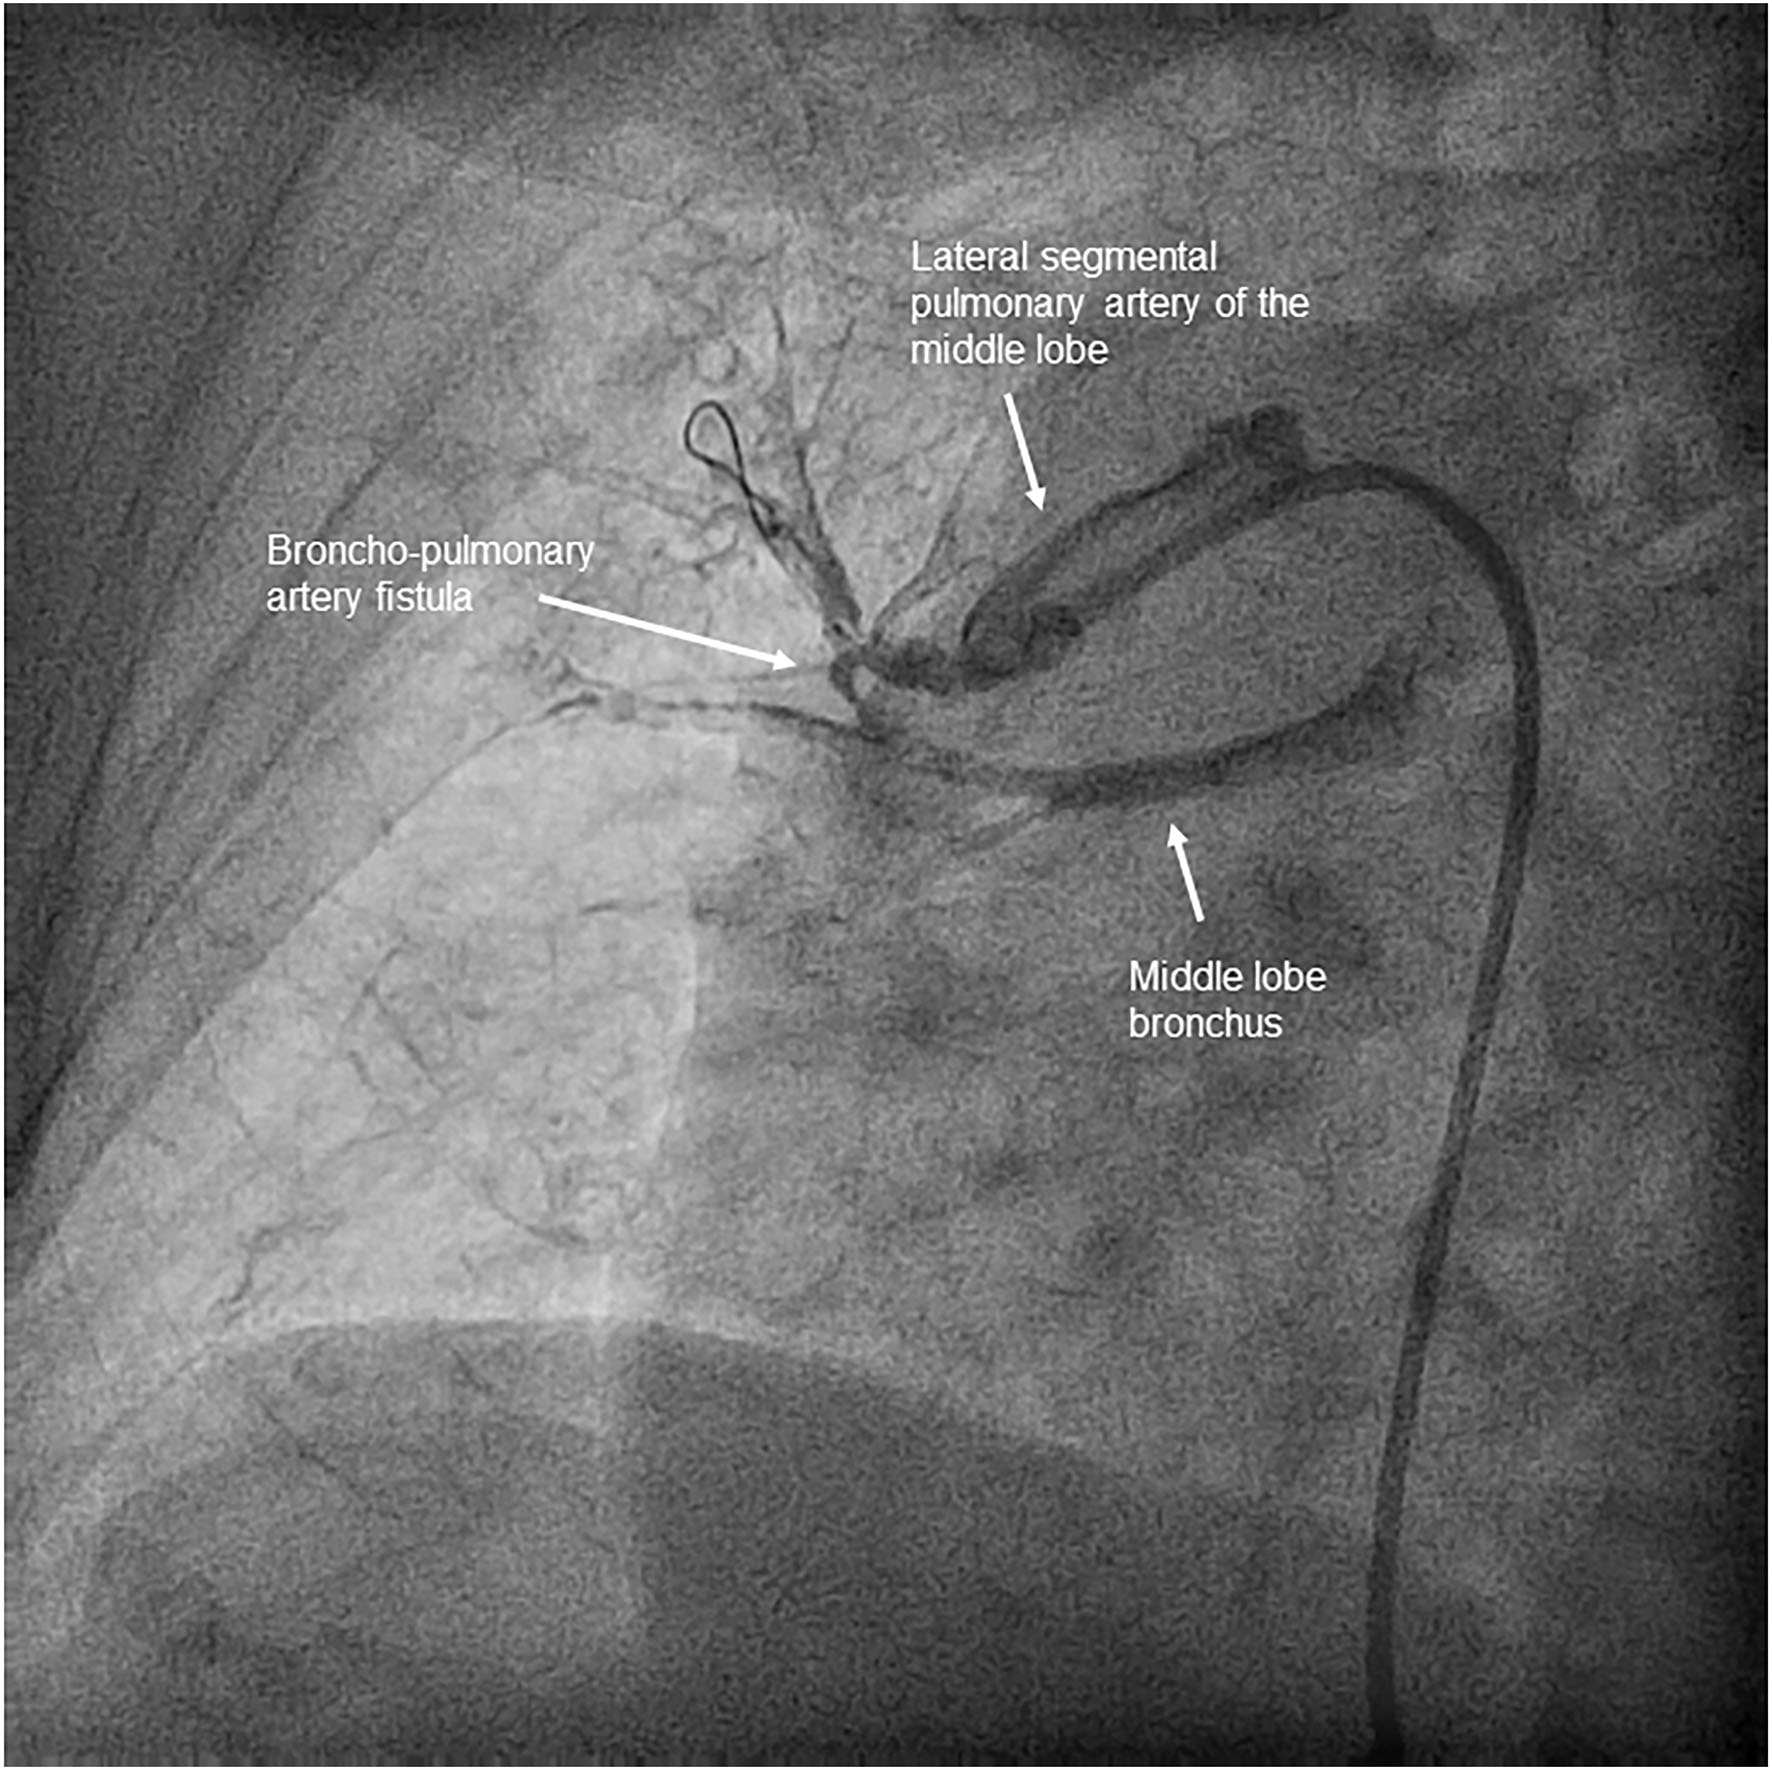

Across all 116 procedures performed on 33 patients, the most common complication was mild hemoptysis, which occurred in 21.2% of the patients throughout the program and in 12.9% of the procedures. This complication was resolved in all patients by stopping the procedure, along with anticoagulation reversal and prolonged balloon inflation when necessary (Supplementary Videos 3–5). None of the patients with this complication required ventilatory or hemodynamic support. One patient underwent covered stent implantation due to a bronchopulmonary artery fistula (Figure 5). The pulmonary injury appeared in 3.4% of the procedures, of which 50% were grade 2 (Figure 6). No patient aged ≥70 years had a grade 5 pulmonary injury. One patient who was admitted to undergo several BPA procedures died 96 h after her first BPA session due to a hemorrhagic stroke while receiving LMWH at an anticoagulant dose (periprocedural mortality, 3%) (Table 5).

Figure 5

Bronchopulmonary artery fistula. Significant contrast leakage from one pulmonary artery branch of the middle lobe to the bronchus, without visible parenchyma extravasation, which appeared after advancing a 2.5 mm balloon without inflation through a subtotal stenosis.